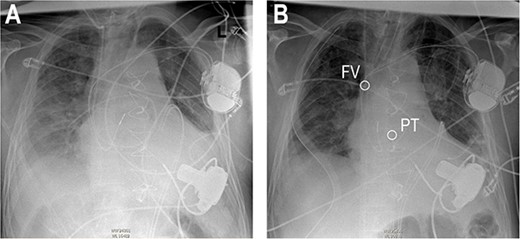

On the second postoperative day the patient showed hemodynamic impairment with signs of right ventricular failure. A temporary percutaneous RVAD was implanted with two cannulas via the right internal jugular vein (IJV) and the right femoral vein (FV). Despite RV support, LVAD flow did not increase and hemodynamic instability failed to improve. Transthoracic echocardiography revealed severe pulmonary insufficiency caused by the cannula of the RVAD. The blood recirculated in the congested right ventricle (Fig. 2, Videos S2 and S3 in the Supplementary Material online).

Anteroposterior thoracic radiography after LVAD implantation (A). Anteroposterior thoracic radiography after RVAD cannulation of the PT (B). Tip of cannula in the right FV, tip of cannula in the PT.